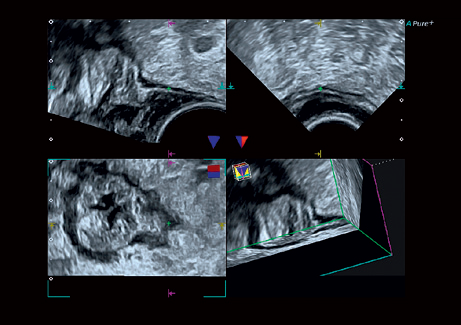

• STIC - исследование сердца плода в режиме объёмной визуализации

• STIC Color - цветная объёмная визуализация сердца плода

• MPR - функция мультипланарной реконструкции для визуализации исследуемой области в 3-х ортогональных плоскостях

• Программа анализа сердца плода в трех проекциях в реальном времени 4D Stick;